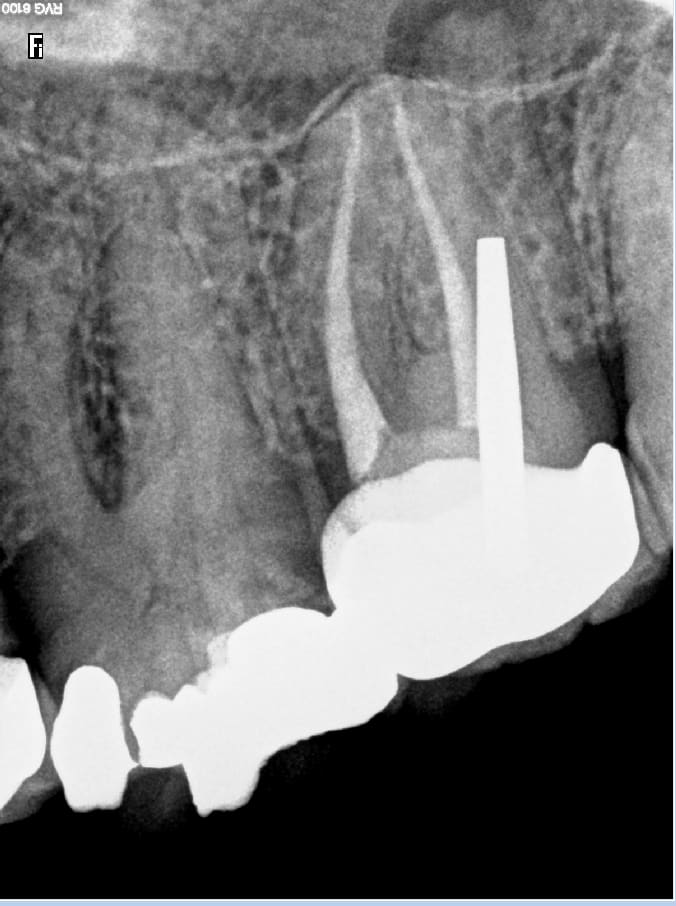

Alors cet enfoiré m'a envoyé la radio.....

Et je lui ai dit : de quoi te mêles tu le patient ne sent rien. -)))

C'était moi le patient. je suis un patient cool. Je n'ai pas voulu mettre mon confrère dans l'embarras. J'ai quand meme été sceptique c'est pour ça que je lui ai demandé de m'adresser la radio de fin de traitement.... Qui ne correspond pas du tout à la radio 7 ans après. Comme quoi éviter de tirer des conclusions hâtives.

Mai 2016. Tiens ? vous avez une lésion à l'apex de 25. J'ai pas mal on laisse. Septembre 2016 débarque en urgence RTE.... octobre 2016 pose ic provisoire. Mai 2019 pose de la définitive. Toi aussi tu lis les posts en diagonale et tu te prends le melon ? -)))

Alors pour répondre à vos questions

j'adresse pour une 46 symptomatique, et le confrère qui n'est pas endo exclusif fait le job, et détecte pour une raison que j'ignore encore des "kystes" sur 24.25. J'ai réalisé sur ces dents un traitement initial sur 24 et un rte sur 25 avec 2 cr en 2013.

Suite à appel du patient, je comprends que les dents sont a priori asymptomatiques, il me parle de traitements qui ne vont pas au bout des racines et d'un instrument fracturé. Il a un devis rte et prothèse et me demande son dossier, souhaite que je prenne en charge tous les frais, ce que je refuse. Je lui ai dit de me faire un courrier il veut absolument faire jouer mon assurance car pour lui j'ai fait des erreurs.